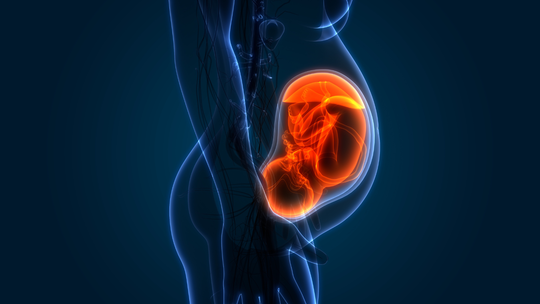

Pregnancy Tips and Guide

"Common Causes of Miscarriage in Early Pregnancy: What You Should Know\",\"imageid\":\"131009054\",\"imgsize\":\"1661384\",\"lu\":\"May 12, 2026, 02:25 PM\",\"id\":131009054,\"dl\":\"May 11, 2026, 03:00 PM\",\"seolocation\":\"pregnancy/causes-of-miscarriage-in-early-pregnancy\",\"subsecname\":\"Pregnancy\",\"subsecmsid\":112886004,\"syn\":\"It is very natural to experience happiness and a little anxiety simultaneously during the early weeks of pregnancy. Concerns about miscarriage are common, and many causes are not within your control. Learning about these can help you feel more supported.\",\"agency\":{\"id\":87654322},\"tn\":\"news\",\"imgratio\":\"0.5625\",\"dm\":\"t\",\"subsecseolocation\":\"pregnancy\",\"host\":\"prega\",\"slot\":\"10\"},{\"hl\":\"How Often Should You Bathe a Newborn Baby?\",\"imageid\":\"131005010\",\"imgsize\":\"35408\",\"lu\":\"May 11, 2026, 01:00 PM\",\"id\":131005010,\"dl\":\"May 11, 2026, 01:00 PM\",\"seolocation\":\"baby/bathing-newborn-baby-how-often-should-you-do-it\",\"subsecname\":\"Baby\",\"subsecmsid\":113631885,\"syn\":\"Bathing your newborn can feel both special and a little overwhelming, especially if you are unsure how often to bathe them. Fortunately, newborns do not require everyday bathing. You can take care of your baby's sensitive skin, make bathing time a peaceful experience, and create a bonding experience by knowing the proper frequency and using safe, gentle bathing techniques.\",\"agency\":{\"id\":87654322},\"tn\":\"news\",\"imgratio\":\"0.5625\",\"dm\":\"t\",\"subsecseolocation\":\"baby\",\"host\":\"prega\",\"slot\":\"11\"},{\"hl\":\"Blood Clots During Pregnancy: Understanding the Risks and Complications\",\"imageid\":\"131002969\",\"imgsize\":\"1495735\",\"lu\":\"May 11, 2026, 11:00 AM\",\"id\":131002969,\"dl\":\"May 11, 2026, 11:00 AM\",\"seolocation\":\"pregnancy/blood-clots-during-pregnancy-risks-symptoms-prevention\",\"subsecname\":\"Pregnancy\",\"subsecmsid\":112886004,\"syn\":\"Blood clots during pregnancy are a serious matter, but the positive part is that they are uncommon and usually preventable with proper awareness and care. Many expectant parents worry about this issue because pregnancy naturally changes how the blood behaves. But understanding the facts helps you stay safe and enjoy this special time.\",\"agency\":{\"id\":87654322},\"tn\":\"news\",\"imgratio\":\"0.5625\",\"dm\":\"t\",\"subsecseolocation\":\"pregnancy\",\"host\":\"prega\",\"slot\":\"12\"},{\"hl\":\"IVF Complications: What Every Couple Should Prepare For\",\"imageid\":\"130957503\",\"imgsize\":\"1771006\",\"lu\":\"May 11, 2026, 09:00 AM\",\"id\":130957503,\"dl\":\"May 11, 2026, 09:00 AM\",\"seolocation\":\"getting-pregnant/ivf-complications-symptoms-and-risks\",\"subsecname\":\"Getting Pregnant\",\"subsecmsid\":112886008,\"syn\":\"In vitro fertilisation (IVF) offers real hope to many couples facing infertility challenges. While the procedure has become much safer over the years, it still carries certain risks and possible complications. Understanding these helps you prepare better and stay alert during the journey.\",\"agency\":{\"id\":87654322},\"tn\":\"news\",\"imgratio\":\"0.5625\",\"dm\":\"t\",\"subsecseolocation\":\"getting-pregnant\",\"host\":\"prega\",\"slot\":\"13\"},{\"hl\":\"Cervical Incompetence: The Silent Cause of Second Trimester Loss\",\"imageid\":\"130956971\",\"imgsize\":\"1233562\",\"lu\":\"May 08, 2026, 07:00 PM\",\"id\":130956971,\"dl\":\"May 08, 2026, 07:00 PM\",\"seolocation\":\"pregnancy/cervical-incompetence-second-trimester-loss\",\"subsecname\":\"Pregnancy\",\"subsecmsid\":112886004,\"syn\":\"For many women, this is their first encounter with a condition called cervical incompetence, and tragically, it often announces itself only after a loss. This walks you through what it is, why it happens silently, how it's diagnosed, and what treatments and monitoring options exist to protect your next pregnancy.\",\"agency\":{\"id\":87654322},\"tn\":\"news\",\"imgratio\":\"0.5625\",\"dm\":\"t\",\"subsecseolocation\":\"pregnancy\",\"host\":\"prega\",\"slot\":\"14\"},{\"hl\":\"Can You Plan a Pregnancy After Recovering From Cancer?\",\"imageid\":\"130956443\",\"imgsize\":\"1165295\",\"lu\":\"May 08, 2026, 05:00 PM\",\"id\":130956443,\"dl\":\"May 08, 2026, 05:00 PM\",\"seolocation\":\"getting-pregnant/pregnancy-planning-after-cancer-treatment\",\"subsecname\":\"Getting Pregnant\",\"subsecmsid\":112886008,\"syn\":\"Planning pregnancy after cancer recovery is possible for many individuals with proper medical guidance. Learn about fertility considerations, safe timing, and expert recommendations to help you make informed, confident decisions about stepping into parenthood.\",\"agency\":{\"id\":87654322},\"tn\":\"news\",\"imgratio\":\"0.5625\",\"dm\":\"t\",\"subsecseolocation\":\"getting-pregnant\",\"host\":\"prega\",\"slot\":\"15\"}]}]}]]\n"])